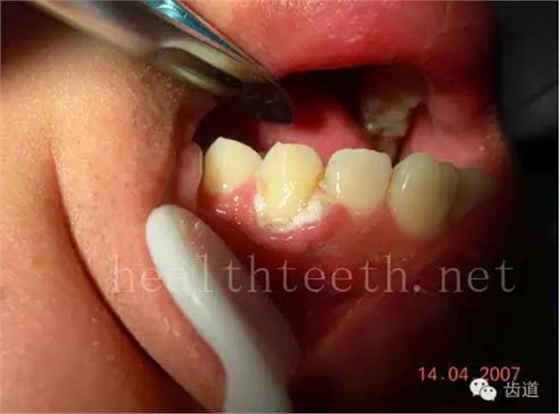

牙周大量牙石堆積